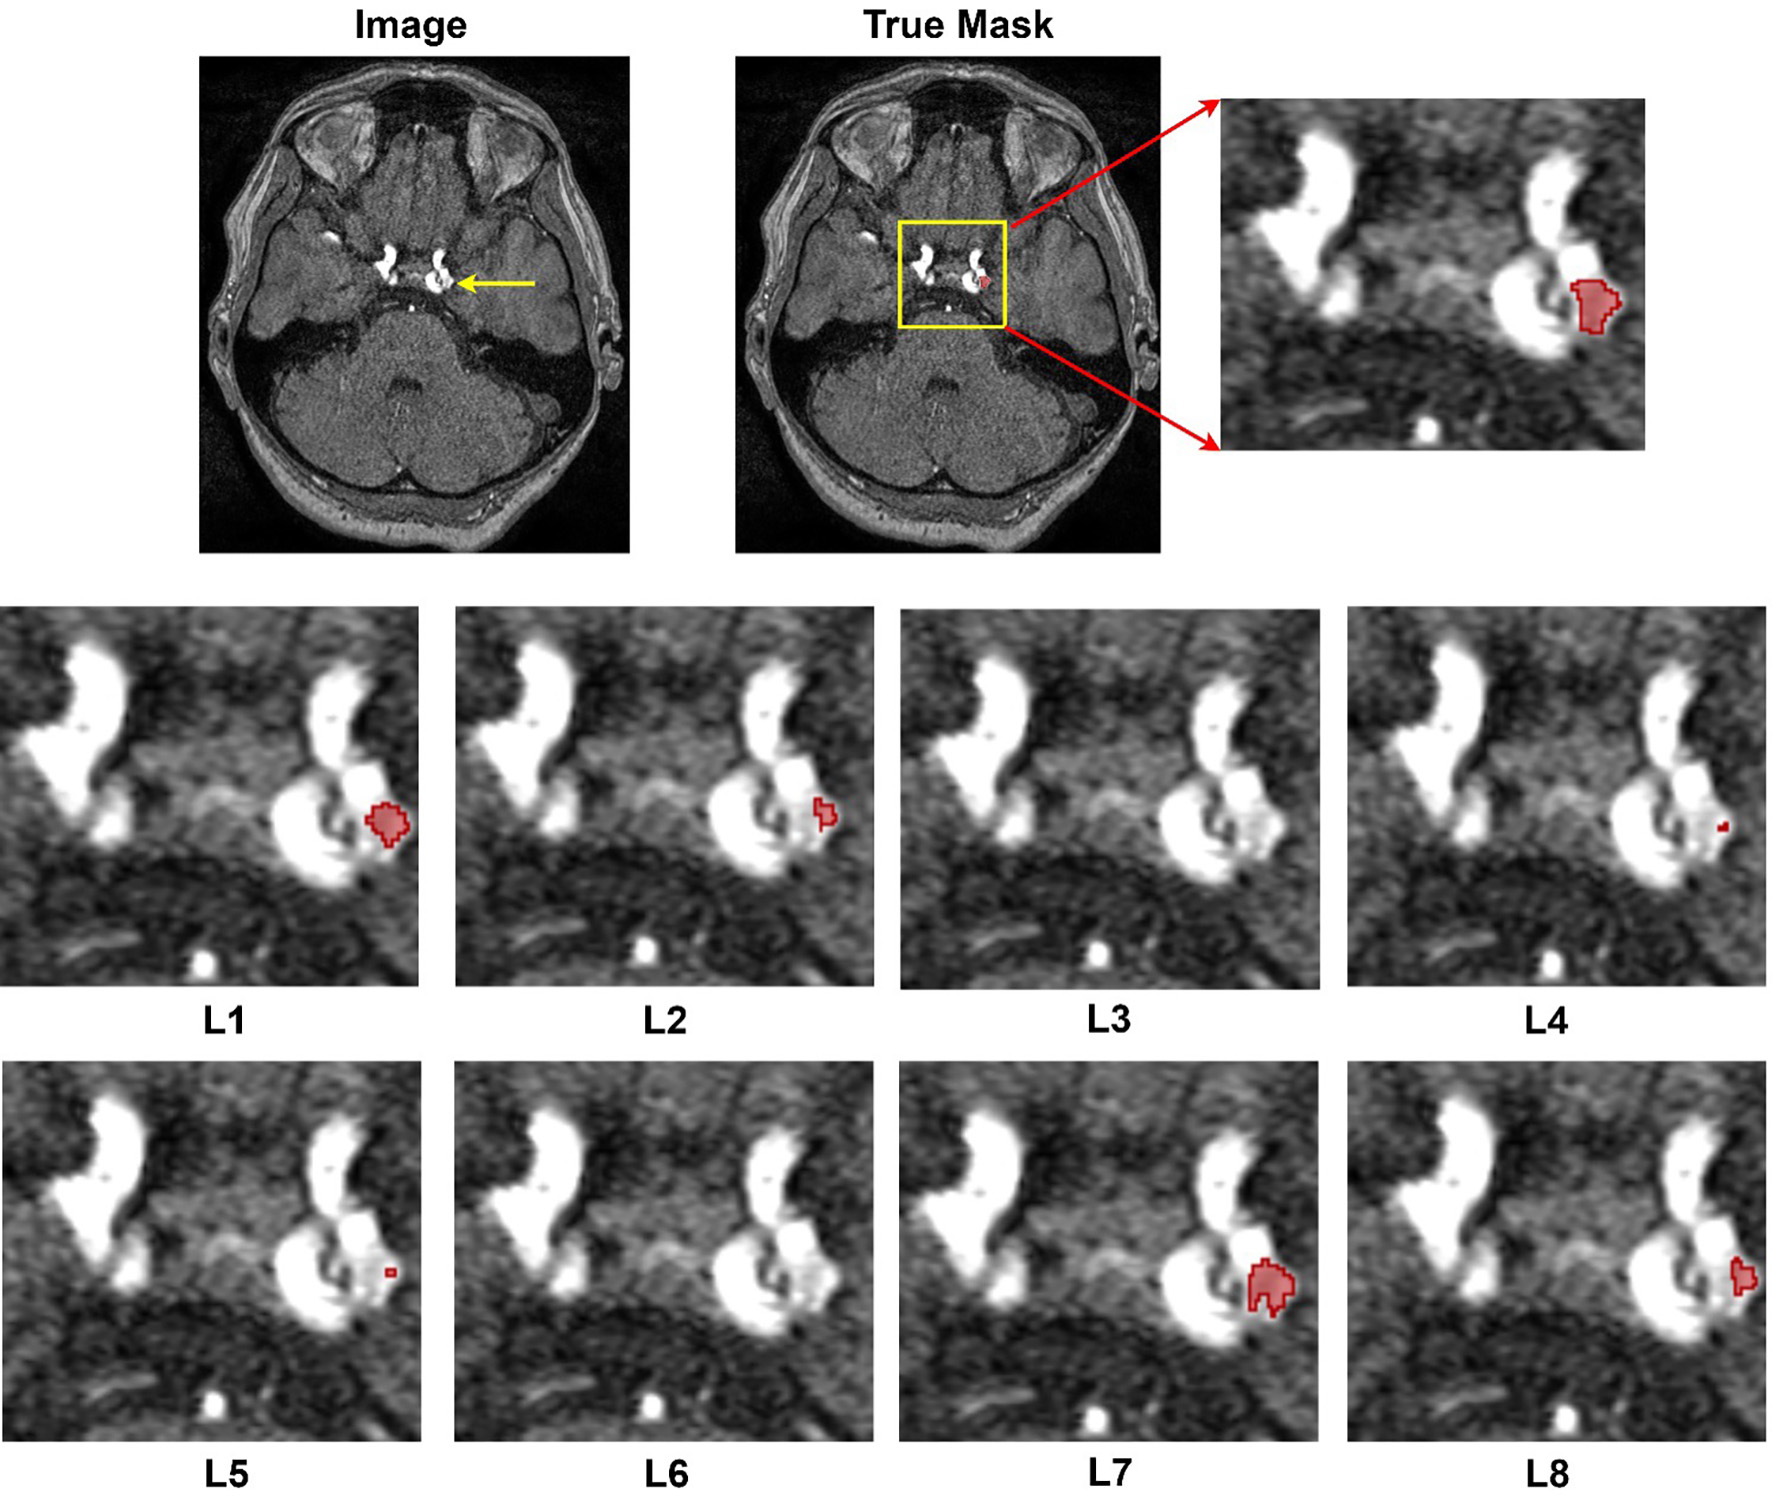

The results from Table 4 showcase the outcomes derived from employing diverse loss functions in the training of nnU-Net for aneurysm segmentation using the RENJI dataset. The Weighted Dice + Top K + CE combination exhibits the highest mean Dice coefficient (0.7219), indicating superior overlap between predicted and ground truth regions. The Weighted Dice + CE + TopK combination achieves the highest sensitivity (0.6948), representing the model's ability to identify true positive instances. In terms of precision (0.8257), reflecting the correctness of positive predictions, Weighted Dice + CE + Top K obtains the highest mean value. For all metrics, the combination of Dice + CE secures the second rank. The variations in these metrics underscore the influence of different loss functions on the model's performance. Notably, Dice + Top k + CE and its weighted variant demonstrate the minimum SD for Dice and Sensitivity, while the combination of Dice and TopK yields the minimum variation in Precision. In summary, akin to the ADAM dataset, the highest performance across all metrics is achieved by combining weighted Dice + CE + TopK, with Dice + CE ranking second. Figure 4 shows the segmentation results of all loss functions on Case #39 from the ADAM dataset. This case was selected because it contains a relatively small aneurysm (~3.5 mm), which represents a challenging scenario for segmentation and thus highlights differences between loss functions.

Figure 4. Segmentation results provided by different losses. Image#39 from ADAM dataset. L1: Dice + CE, L2: Dice + Top k, L3: Dice + CE + Top k, L4: Dice + Focal, L5: Dice + Top K + Focal, L6: Dice + Top k+ Focal + Tversky + CE, L7: Weighted Dice + Top k+ CE, and L8: Weighted Dice + Top k+ Focal + Tversky + CE.